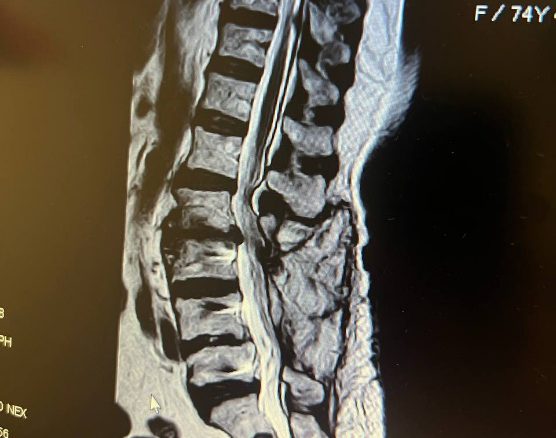

بمرور الوقت، تسبب آلام الظهر هذه الناتجة عن الوضعية الثابتة والطويلة تغيرات في سطح المفصل الفقري والأقراص القطنية وتجعل الشخص عرضة لبروز القرص القطني والتهاب المفاصل بين الفقرات وأخيرًا تضيق القناة الشوكية. يمكن أن تكون زيادة الوزن سبباً آخر لآلام الظهر لدى الأشخاص، خاصة إذا كان الشخص يعاني من السمنة المفرطة أكثر في منطقة البطن. إن عدم وجود توازن مناسب بين عضلات الظهر والبطن والوركين هو سبب آخر للإصابة بآلام الظهر قصر مجموعة من العضلات مقابل ضعف مجموعة أخرى من العضلات، وهو ما يجب فحصه من قبل أخصائي العلاج الطبيعي لمنع تقدمه. ومن الأفضل الذهاب إلى مركز العلاج الطبيعي في المراحل الأولى من ظهور الأعراض، حتى يمكن الوقاية من تطورها إلى آلام عرق النسا، أو إحالة الساقين، أو الوخز، أو الوخز، أو حتى تنميل الأطراف، وذلك من خلال تشخيص الأسباب بشكل أسرع. من خلال التقييم السريع وفهم مشاكل العضلات والعظام، سيقوم أخصائي العلاج الطبيعي بتخطيط خطة العلاج الخاصة بك لتصحيح وضعك واستخدام طرق العلاج الكهربائي بما في ذلك: المحفز، العلاج بالموجات فوق الصوتية، العلاج بالليزر، العلاج بالمغناطيس, العلاج الحراري، العلاج الحراري، العلاجات اليدوية أو اليدوية، الوخز بالإبر الجافة أو النقر، التدليك، الوخز بالإبر الكهربائي اعتمادًا على درجة الالتهاب وتورط المنطقة المصابة وأخيرًا سيعلمك بعناية التمارين الصحيحة. وفي الوقت نفسه، سيبلغونك بالتوصيات اللازمة لمنع تطور آلام الظهر أو تكرارها. مركز العلاج الطبيعي يستطيع توان نافين، باستخدام أفضل المعدات الحديثة وأفضل طرق العلاج تحت إشراف أخصائي العلاج الطبيعي الخبير نوشين ألفانديان، مساعدة الأشخاص الذين يعانون من آلام الظهر أو أي نوع من آلام الظهر على التعافي بشكل أسرع.